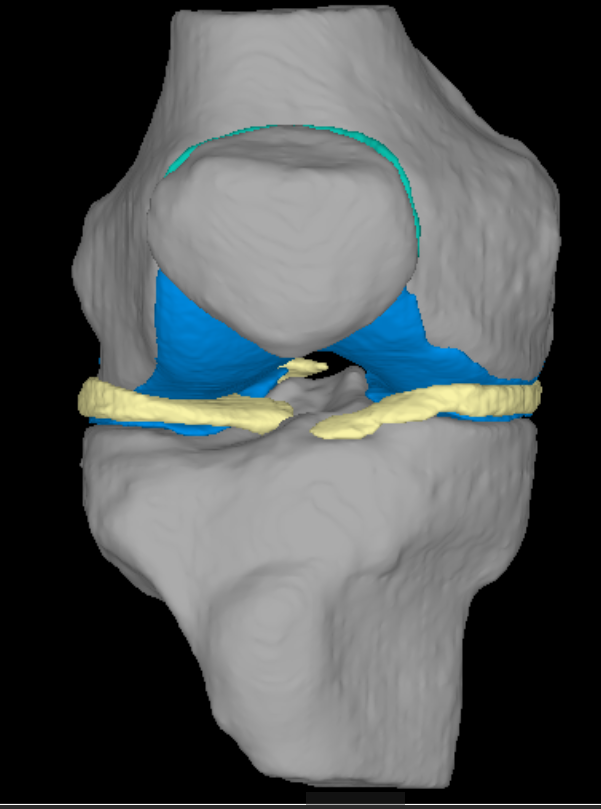

CT検査

当院では、Canon製Aquilion Prime SP 80列を使用しています。短時間で広範囲の撮影ができる他に、撮影したデータを元に任意の角度に合わせた断面像を生成したり、骨や臓器を3次元的に表示して観察することができます。また当院では3D医用画像処理ワークステーション(ZIO・VINCENT)を導入しており、より詳細な3次元画像の作成を行っています。